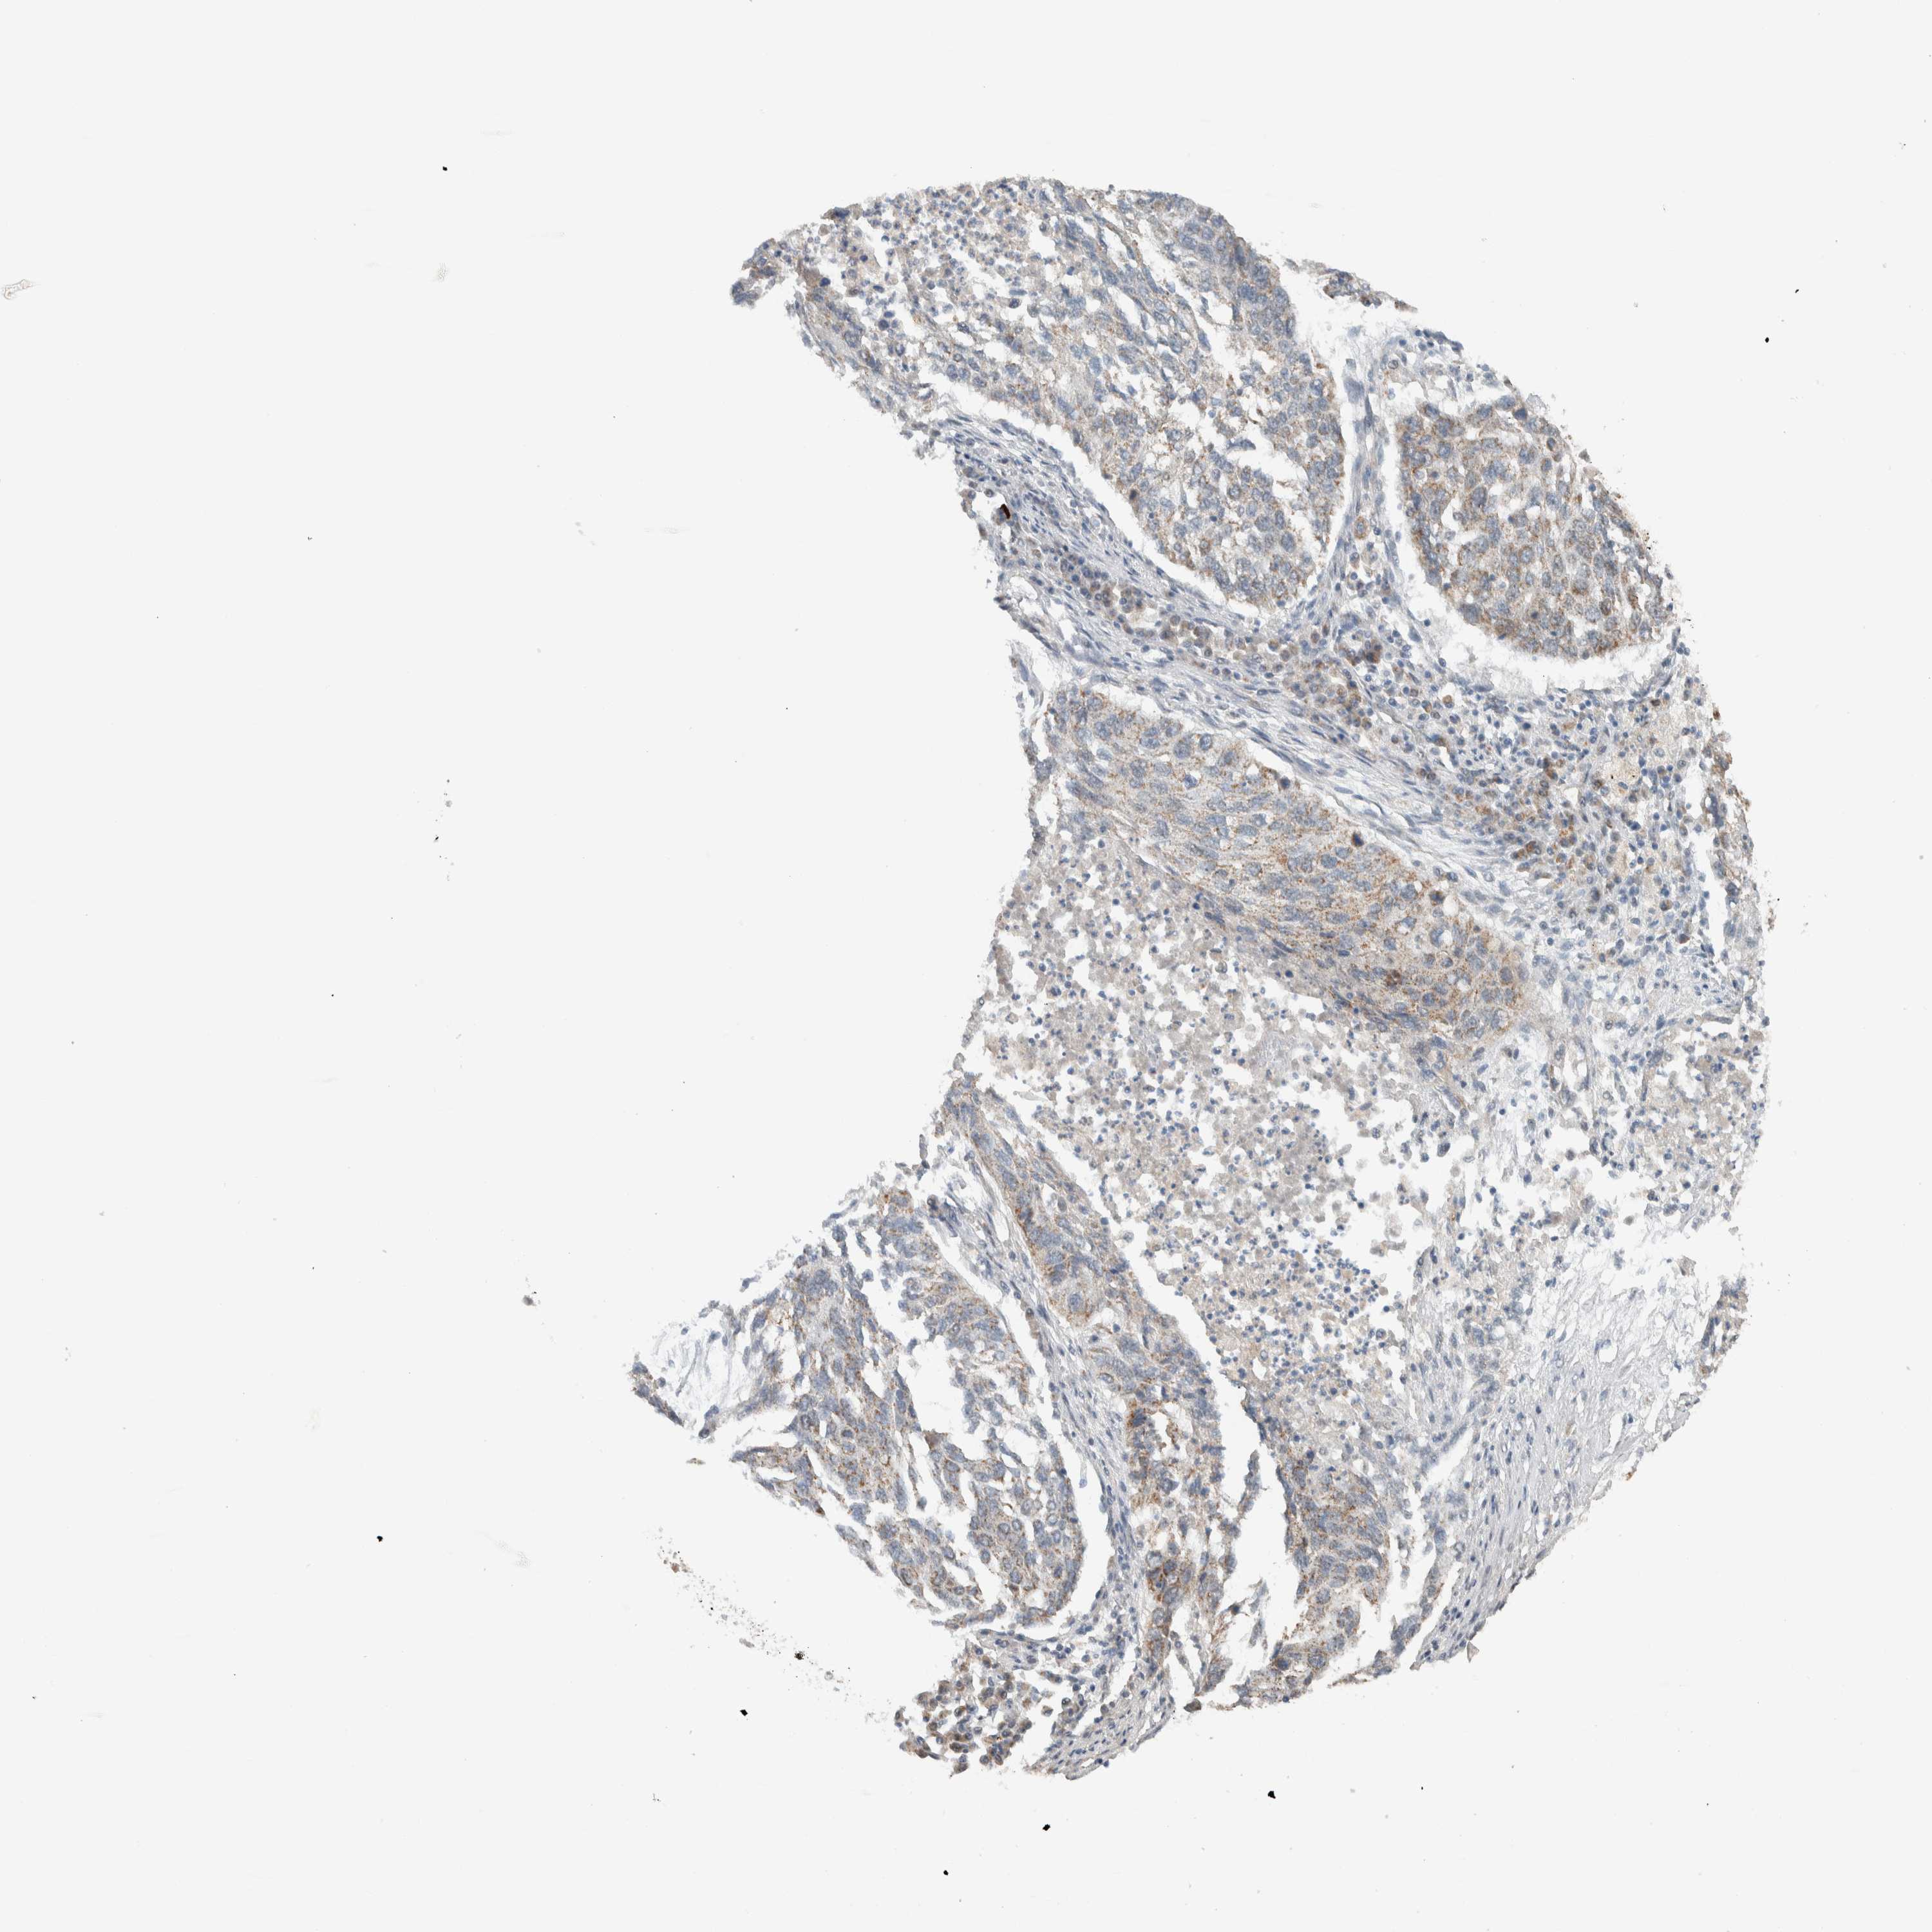

LUNG SQUAMOUS CELL CARCINOMA (TCGA) - Interactive survival scatter ploti

The Survival Scatter plot shows the clinical status (i.e. dead or alive) for all individuals in the patient cohort, based on the same data that underlies the corresponding Kaplan-Meier plots. Patients that are alive at last time for follow-up are shown in blue and patients who have died during the study are shown in red.

The x-axis shows the expression levels (FPKM) of the investigated gene in the tumor tissue at the time of diagnosis. The y-axis shows the follow-up time after diagnosis (years). Both axes are complimented with kernel density curves demonstrating the data density over the axes. The top density plot shows the expression levels (FPKM) distribution among dead (red) and alive patients (blue). The right density plot shows the data density of the survived years of dead patients with high and low expression levels respectively, stratified using the cutoff indicated by the vertical dashed line through the Survival Scatter plot. This cutoff is automatically defined based on the FPKM cutoff that minimizes the p-score. The cutoff can be changed by dragging the vertical line or by entering a cutoff value in the square labeled "Current cut-off".

Under the Survival Scatter plot the p-score landscape (black curve; left axis) is shown together with dead median separation (red curve; right axis). Dead median separation is the difference in median mRNA expression between patients who have died with high and low expression, respectively. It is calculated as follows: median FPKM expression of dead patients with high expression - median FPKM expression of dead patients with low expression. This is intended to aid the user in visually exploring custom cutoffs and the associated p-scores and dead median separation.

Individual patient data is displayed and can be filtered by clicking on one or more of the category buttons on the top of the page. Categories describing expression level and patient information include: high, low, alive, dead, female, male and tumor stages. The scale of the x-axis can be toggled between linear and log-scale by clicking on the "x log" button. Mouse-over function shows TCGA ID, patient information and mRNA expression (FPKM) for each patient.

& Survival analysisi

Kaplan-Meier plots summarize results from analysis of correlation between mRNA expression level and patient survival. Patients were divided based on level of expression into one of the two groups "low" (under cut off) or "high" (over cut off). X-axis shows time for survival (years) and y-axis shows the probability of survival, where 1.0 corresponds to 100 percent.

MRPL41 is not prognostic in Lung Squamous Cell Carcinoma (TCGA)